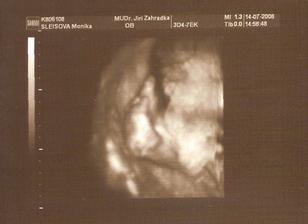

14.7. 3D utz - nádherný zážitek. i když mrňousek moc nespolupracoval a pořád se schovával. Navíc je v plodovce asi dost šupinek mázku, tak jsou fotečky neostré. I tak to bylo krásný. A podle statistik máme termín 12.10. 😲